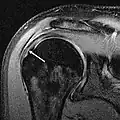

MRT einer kompletten Ruptur -

Die Magnetresonanztomographie, gegebenenfalls mit intraartikulärer (direkt in das Gelenk verabreichter) Kontrastmittelgabe („MR-Arthrographie“), zeigt sehr genau zerstörte Strukturen auf und gehört mittlerweile zu den Standarduntersuchungen bei Schultergelenksläsionen.[14]